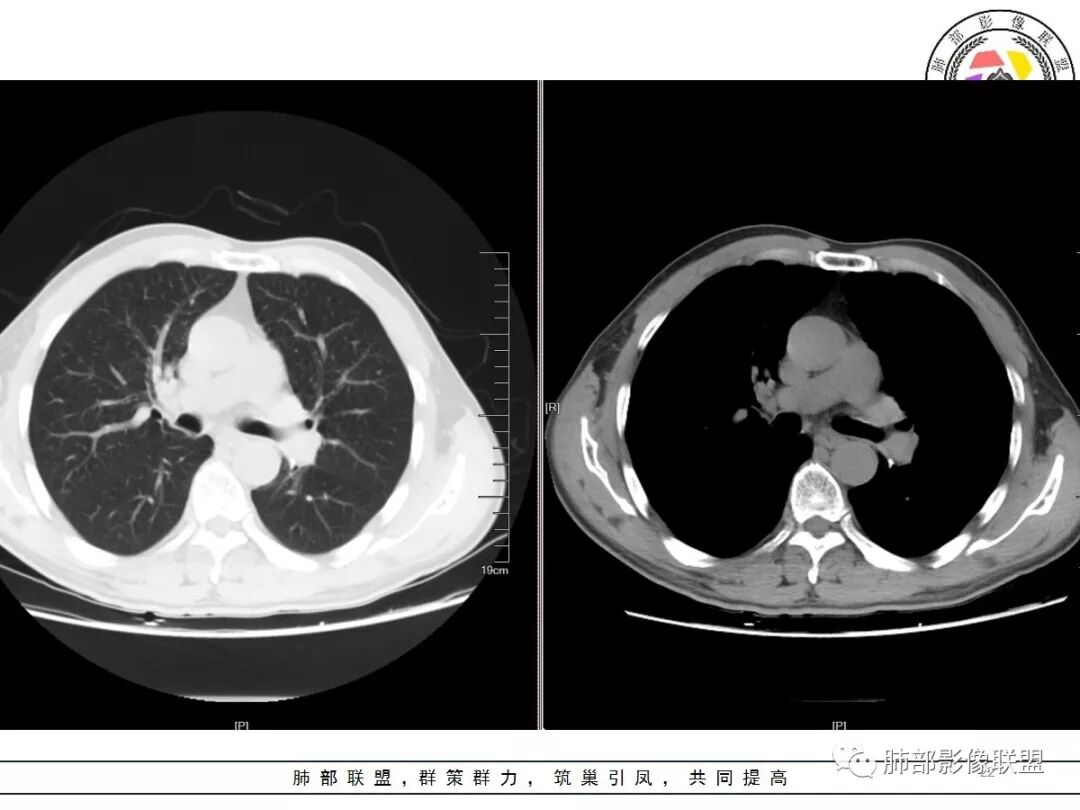

结果

肺结核

病例小结:

1.应该是双肺上叶多发结节,散在大小不等,密度不均,左上纵隔旁病灶环形强化,似乎都符合结核灶。

2.焦点在乎右肺上叶那个有点另类、有点儿一本正经的结节,密度均匀,未见支气管进入,部分圆隆浅分叶,长毛刺或棘状突起,胸膜有点牵拉,像个特立独行的新生物吗?

3.最不支持腺癌的一条是强化程度太轻。此外分叶不典型,还有那条牵张于肺表面的长长的细线影,不大像是在牵拽。

4.小结节新生物不大容易观察到液化坏死,如观察到液化坏死更容易想到的也是结核。

因此,完全排除肺鳞癌还有相当难度的。